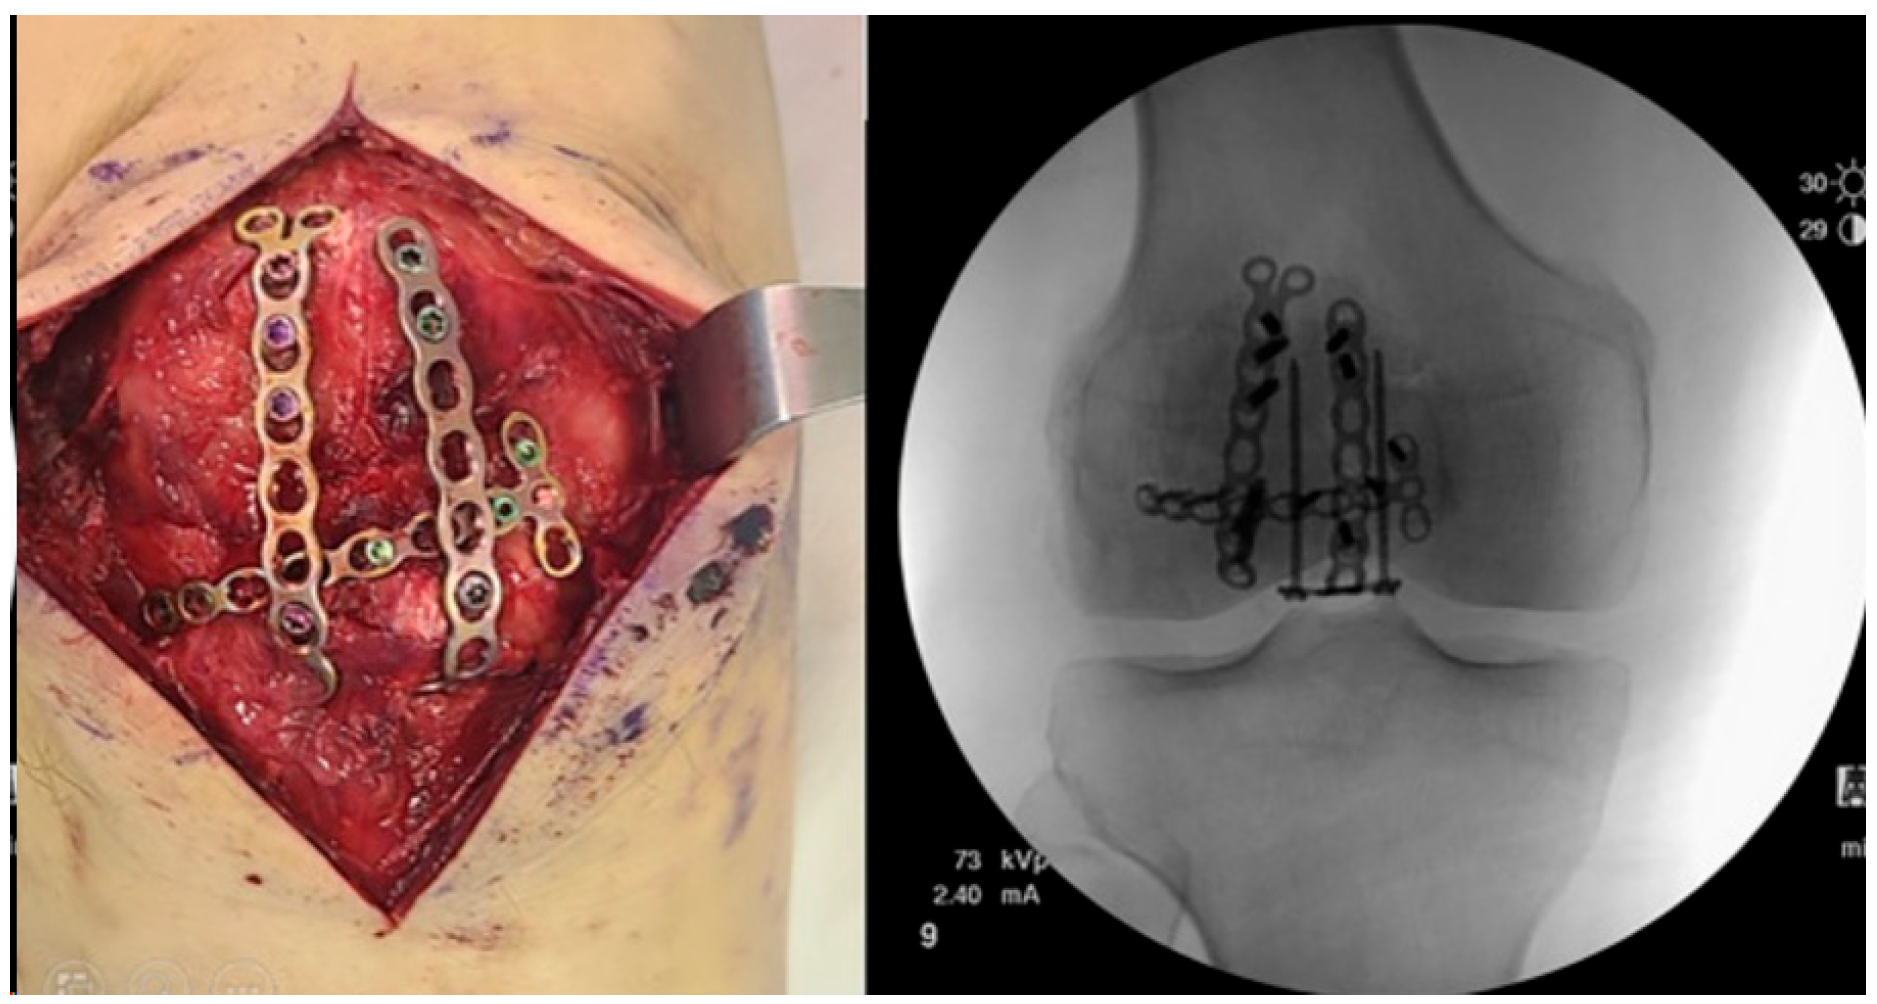

2.5. Locking Plates

- Wild, M.; Fischer, K.; Hilsenbeck, F.; Hakimi, M.; Betsch, M. Treating patella fractures with a fixed-angle patella plate-A prospective observational study. Injury 2016, 47, 1737–1743. [Google Scholar] [CrossRef] [PubMed]

- Buschbeck, S.; Götz, K.; Klug, A.; Barzen, S.; Gramlich, Y.; Hoffmann, R. Comminuted AO-C3 fractures of the patella: Good outcome using anatomically contoured locking plate fixation. Int. Orthop. 2022, 46, 1395–1403. [Google Scholar] [CrossRef]

- Kumar, S.; Mittal, S.; Manhas, V.; Sharma, V. Functional and radiological outcomes following plating for displaced fractures of the patella: A pilot study. Injury 2022, 53, 691–697. [Google Scholar] [CrossRef] [PubMed]

- Yoo, S.J.; Ok, S.; Lee, J.; Choi, S. Can multiple miniplates improve the treatment of comminuted patellar fracture? BMC Musculoskelet. Disord. 2023, 24, 936. [Google Scholar] [CrossRef] [PubMed]

- Amin, A.; Kellam, P.J.; Warner, S.J. Treatment of a Multifragmentary Patella Fracture Using a Novel Anatomic Locking Plate. J. Orthop. Trauma 2022. [Google Scholar]